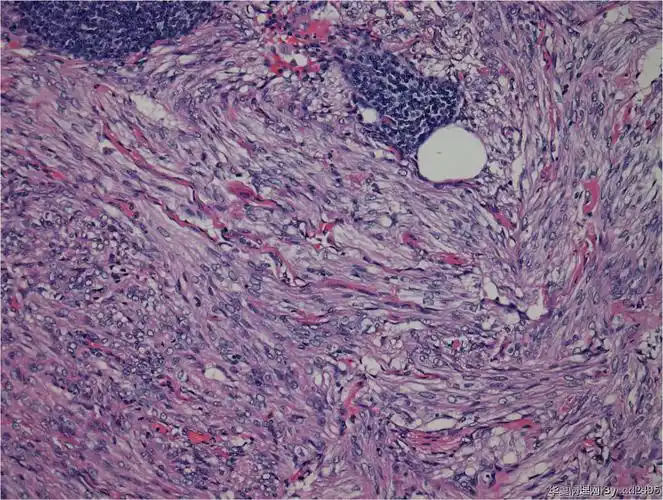

组织学形态由增生的梭形细胞构成,肿瘤细胞可排列成束状,波浪状,车辐